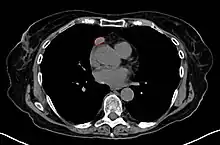

Imaging

A chest X-ray may identify widening of the mediastinum suggestive of thymoma, but computed tomography (CT) or magnetic resonance imaging (MRI) are more sensitive ways to identify thymomas and are generally done for this reason.[38] MRI of the cranium and orbits may also be performed to exclude compressive and inflammatory lesions of the cranial nerves and ocular muscles.[39]

As thymomas are seen in 10% of all people with the MG, people are often given a chest X-ray and CT scan to evaluate their need for surgical removal of their thymus and any cancerous tissue that may be present.[18][37] Even if surgery is performed to remove a thymoma, it generally does not lead to the remission of MG.[49] Surgery in the case of MG involves the removal of the thymus, although in 2013 there was no clear indication of any benefit except in the presence of a thymoma.[53] A 2016 randomized controlled trial, however, found some benefits.[54]